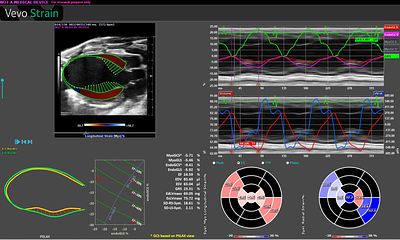

Systems Physiology & Phenotyping Core

The Center performs procedures and quantifies cardiac function for the investigators in the Center, as well as others on campus. Our expertise and suite of instruments enables robust educational opportunities for trainees and faculty.